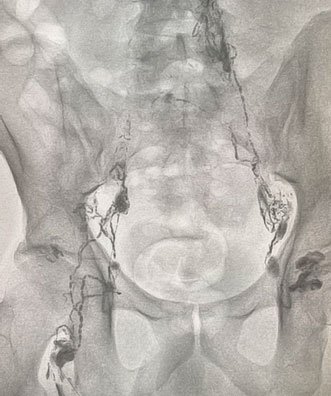

Chylous leak

Dye travelling upwards from lymph nodes